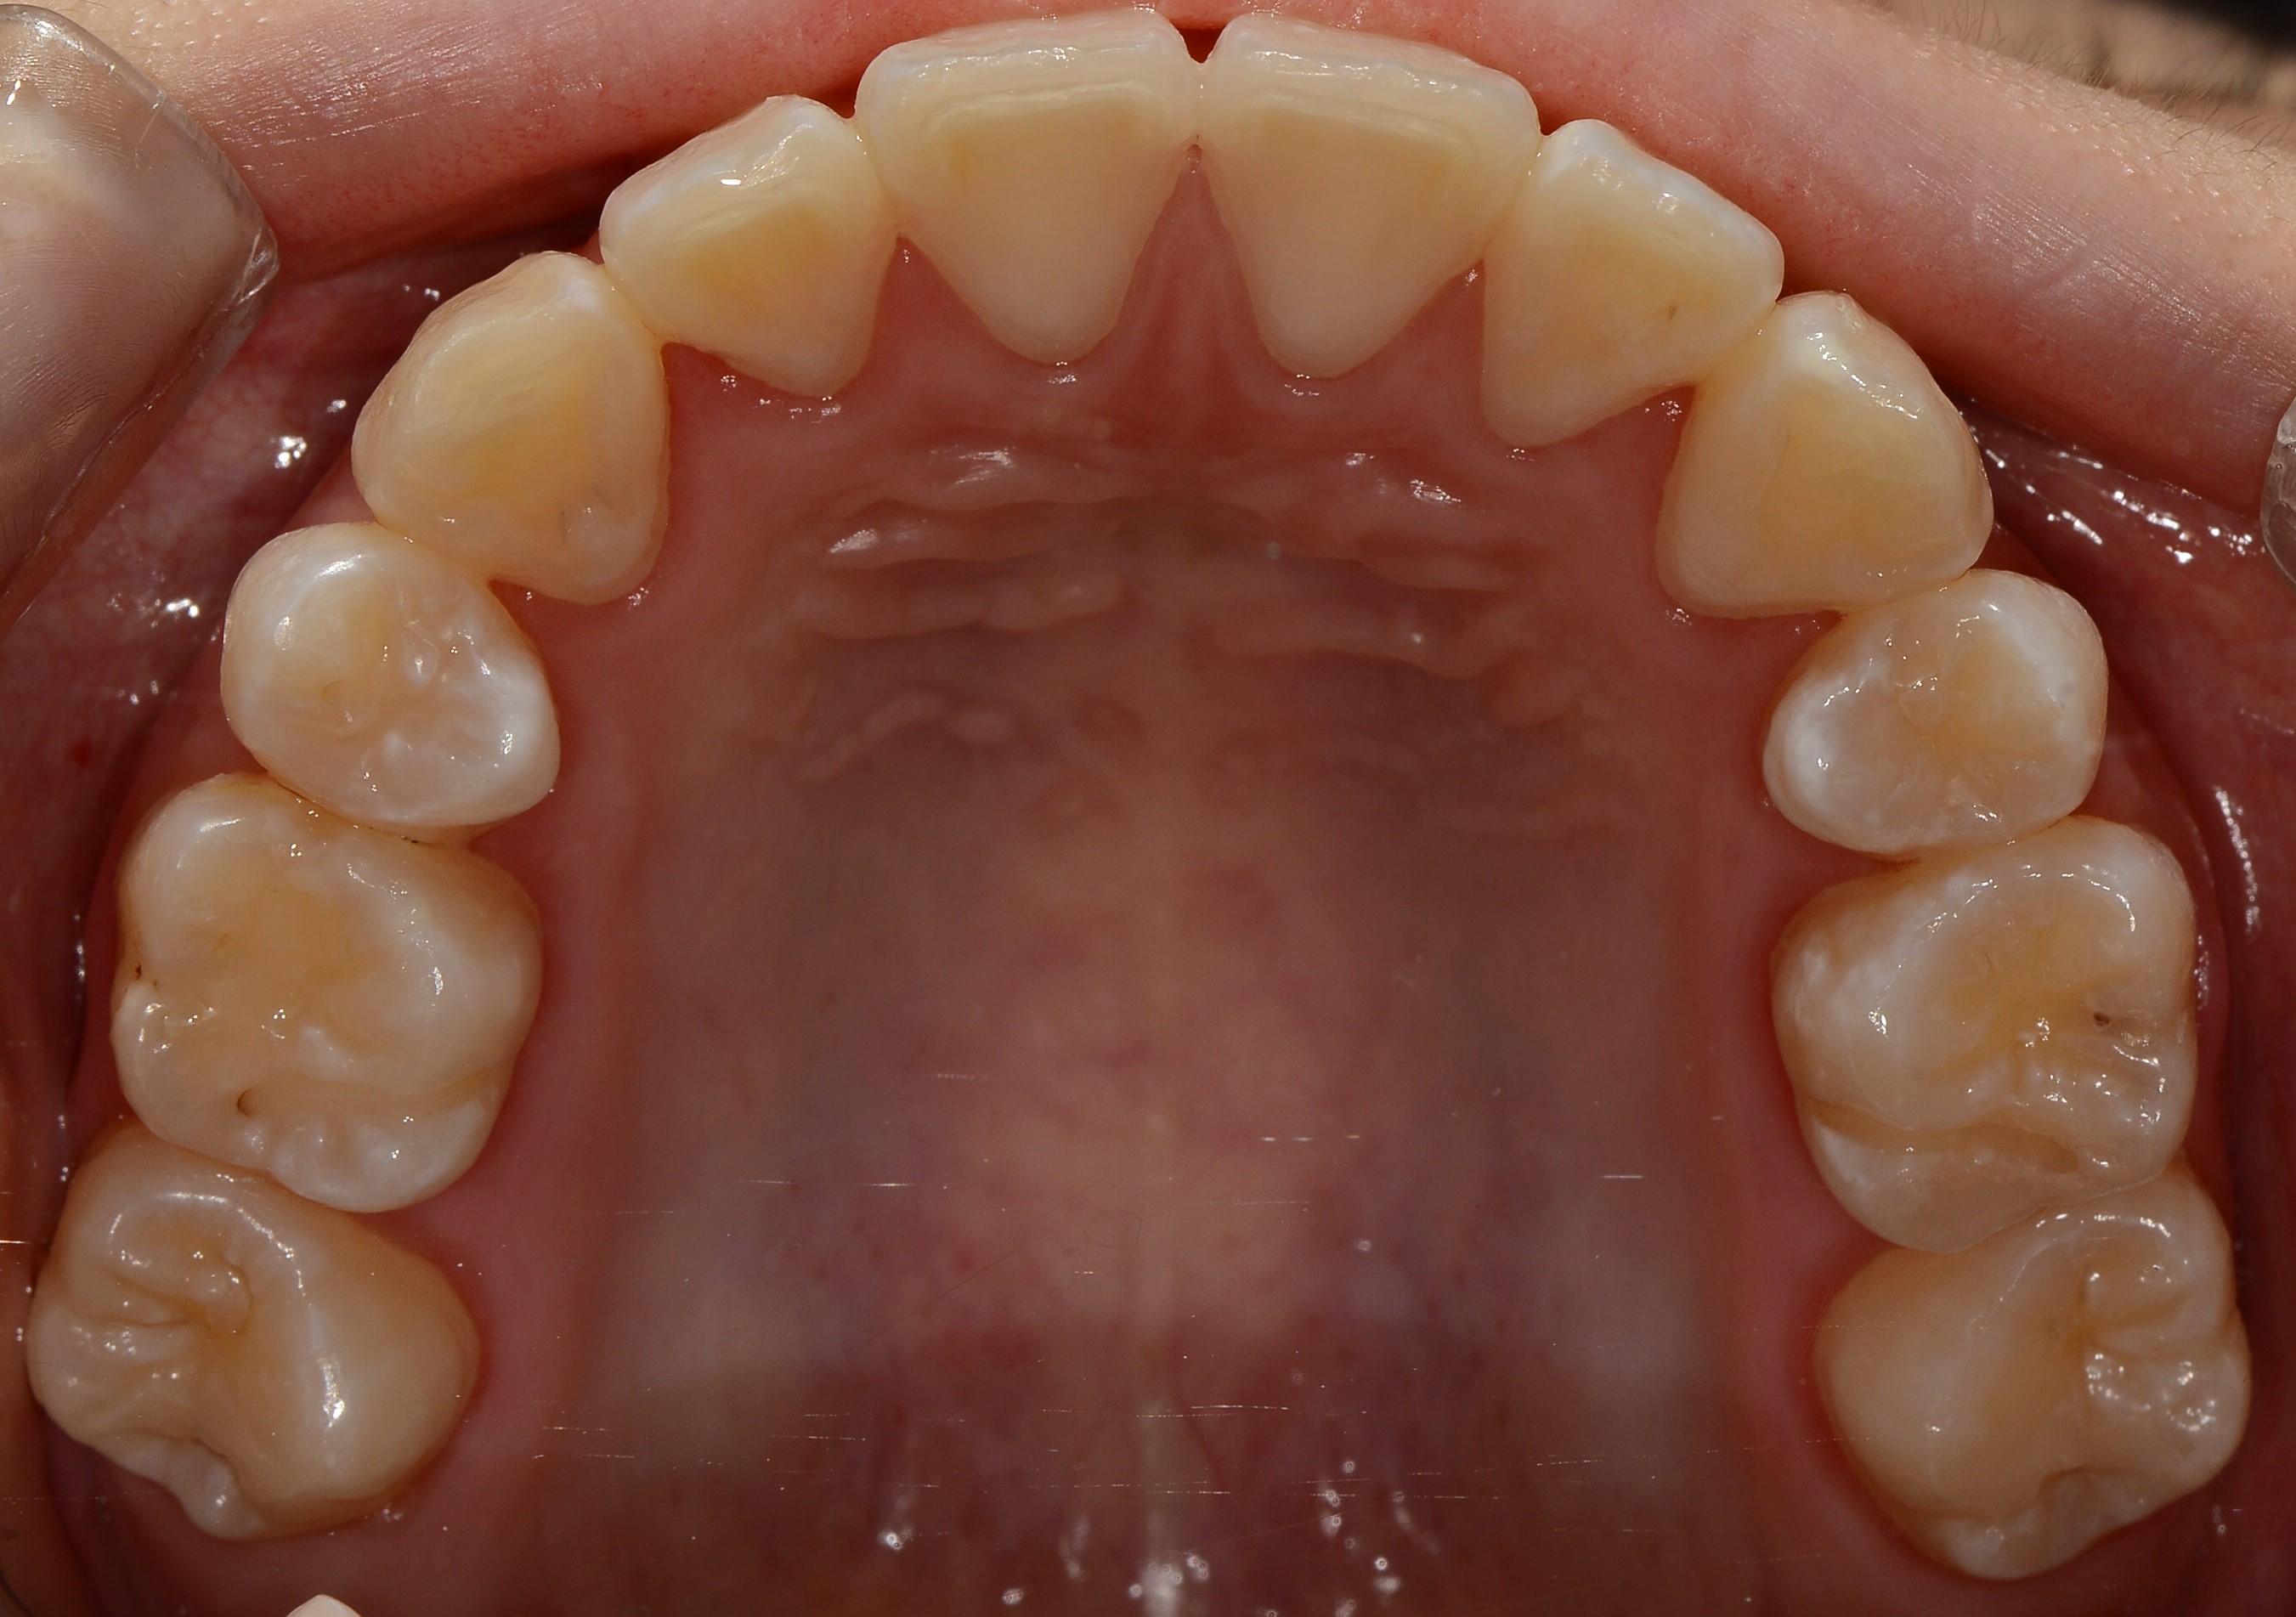

치료 전 사진입니다.